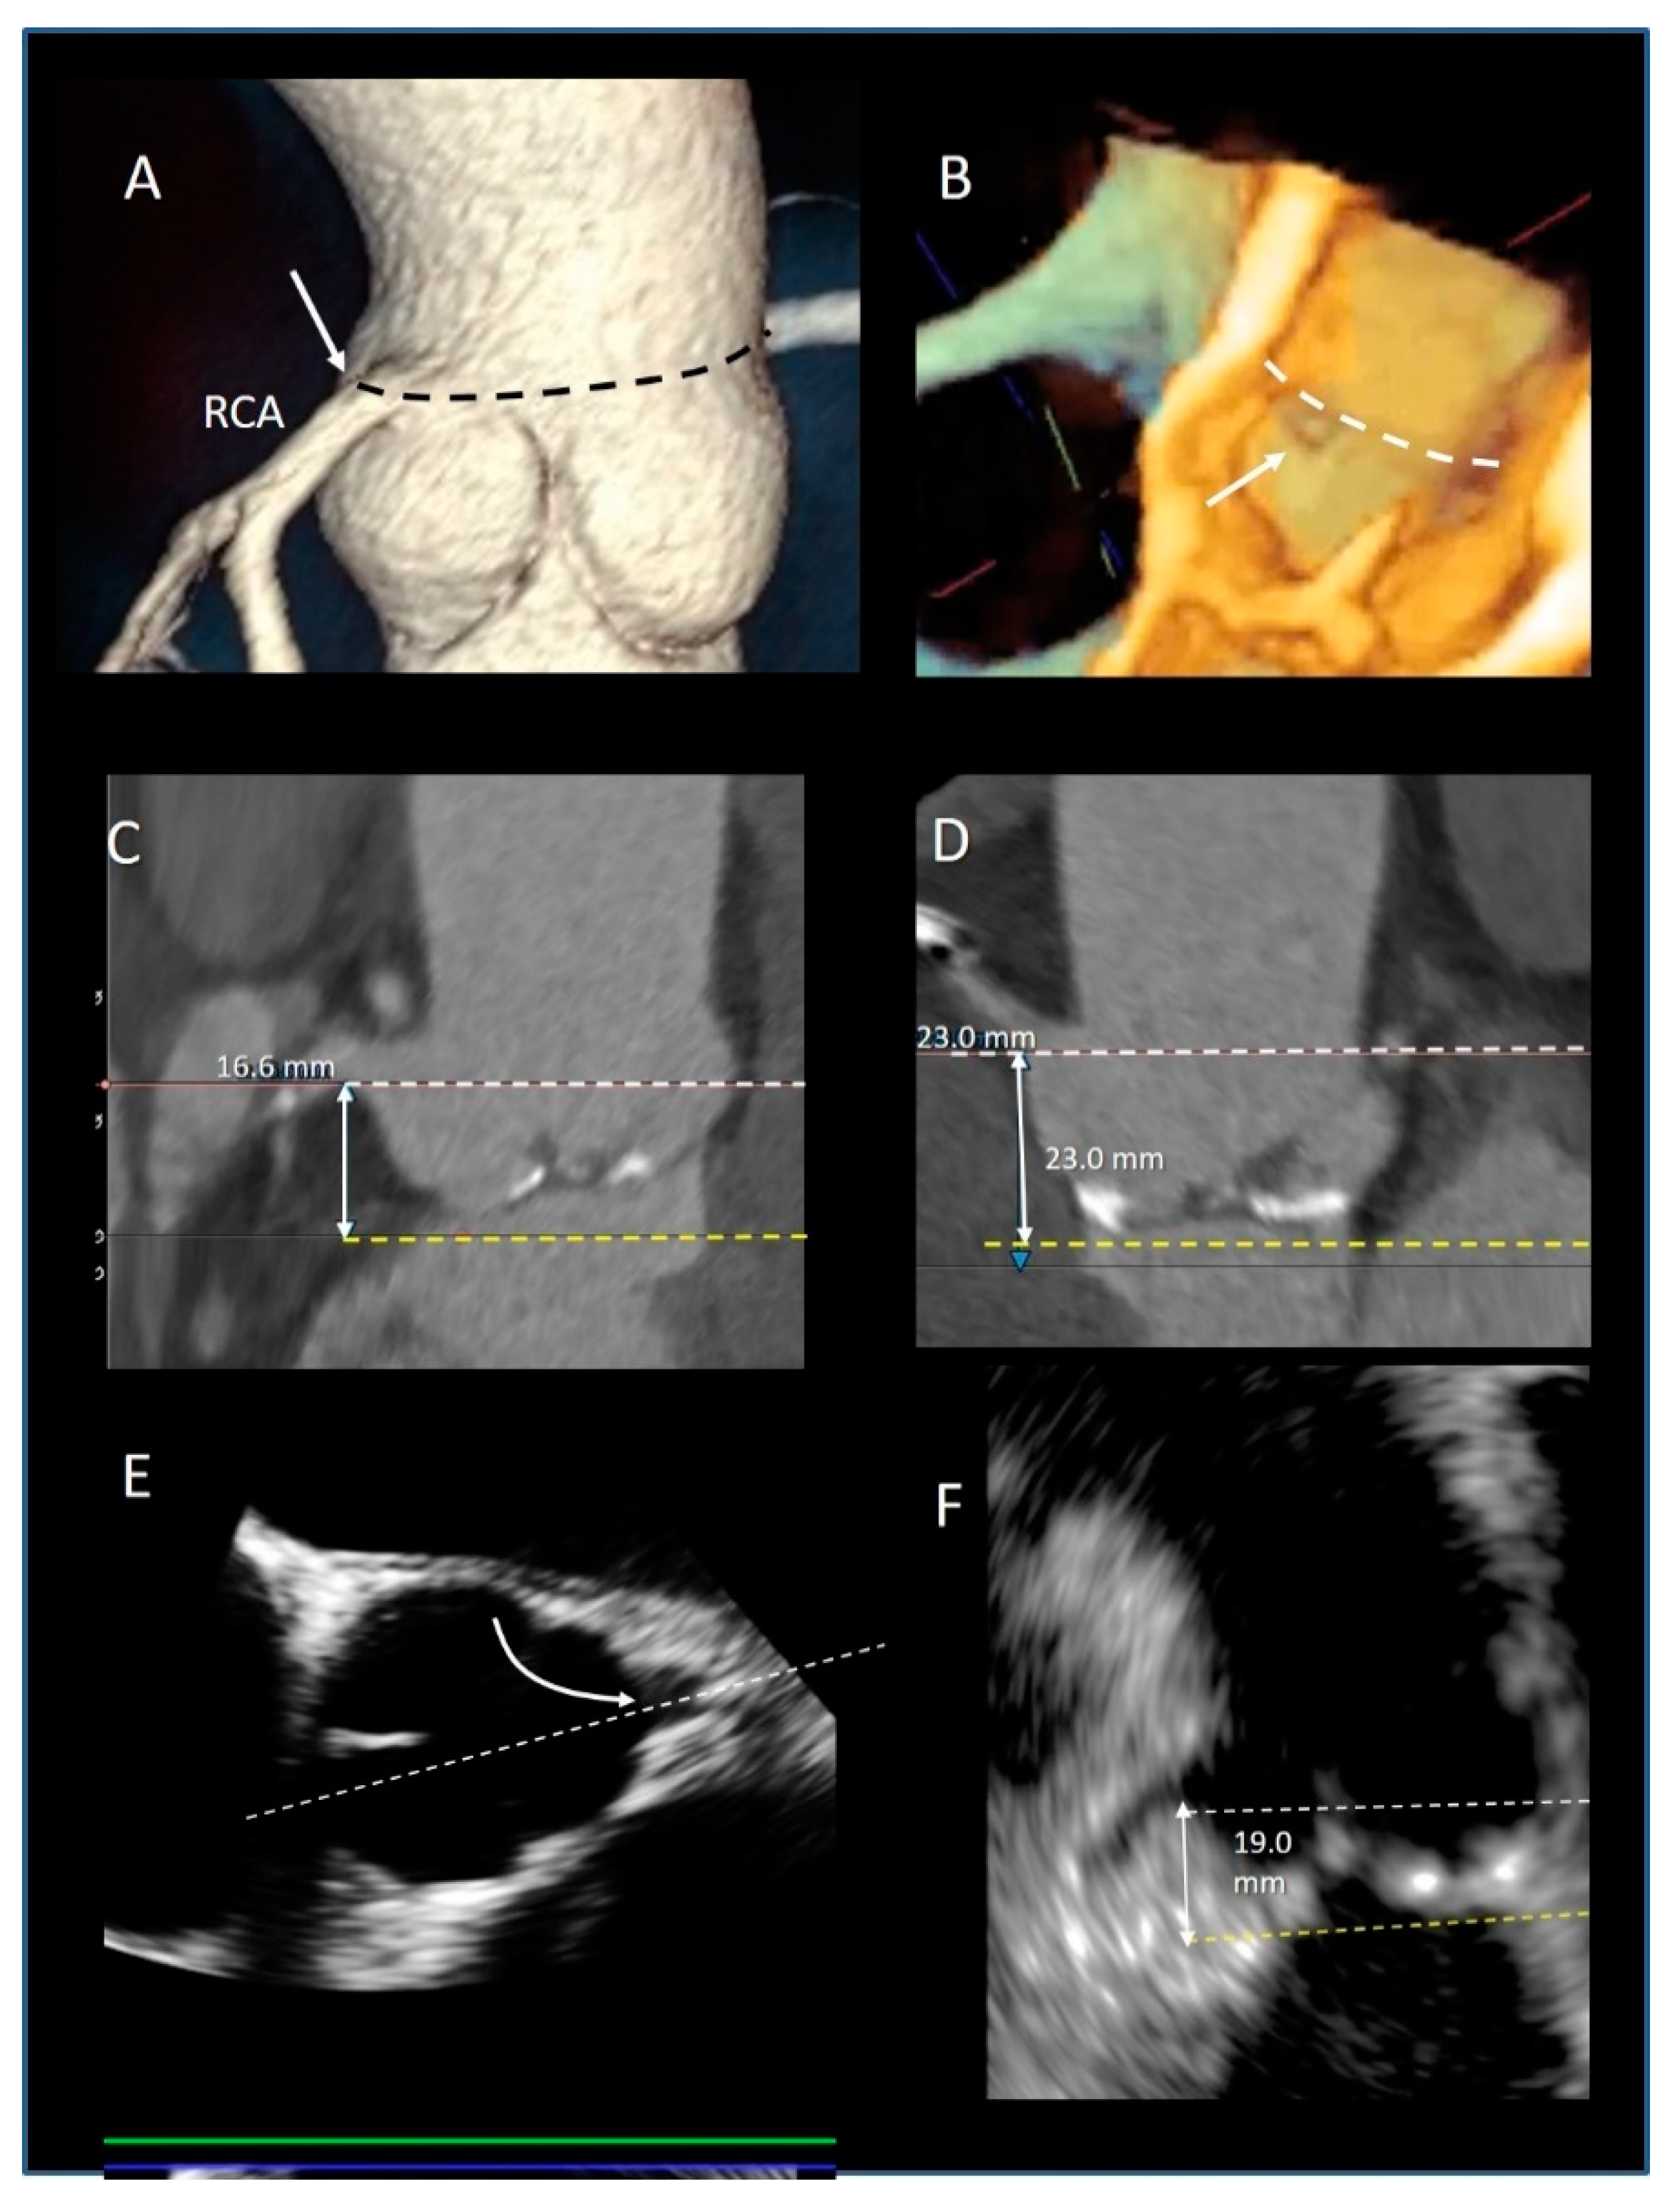

| Ventricular–arterial junction | The term ventricular–arterial junction describes the border between the ventricular myocardium and the fibroelastic structure of the aortic root. Contrary to the right AV junction, where the pulmonary root is entirely supported by the muscular infundibulum, only the left and the right coronary sinuses are partially supported by the myocardium (see text), being the remaining extent of the aortic root supported by fibrous tissue (MS = membranous septum; see text and references [12,13]). | ![]() |

| Cusps, leaflets | The term “cusps” refers to the moving parts of the aortic root. When seen in closed position from the ventricular perspective, this component is similar to the surface of a molar tooth (called cusp). The term is used to describe the structure of the valve (i.e., unicuspidal, bicuspid, and tri-cuspid). Literally the term indicates a pointed end where two curves meet. In the aortic root, it indicates an intact interleaflet triangle with its apex reaching the sinutubular junction. The term leaflet means “small leaf”, which describes a thin, pliable layer. This term perfectly fits the leaflet aspect. N = non-coronary, L = left coronary, R = right coronary leaflets/cusps. | ![]() |

| Commissures | In the anatomy of the aortic root this term refers to the most distal area where the insertions of the leaflets on the aortic wall join each other. | ![]() |

| Aortic annulus | The aortic annulus is the three-dimensional line that follows the hinge line of the leaflets on the aortic wall. This line of dense connective tissue has a crown-shaped appearance (white dotted line). | ![]() |

| Virtual or “echocardiographic” annulus | This term refers to a circumference that joins the lowest points of the leaflet insertion. Although neither anatomically or histologically recognizable, this term has become relevant in the TAVI era. Measurements of this virtual basal plane are used for the sizing of the valve in tricuspid valves. This virtual annuls does not have an anatomic counterpart. | ![]() |

| Surgical annulus | Surgeons fix the prosthetic valves on a circular area lying between the nadirs of the sinuses and midway to the commissures (the aortic prostheses have a flat sewing ring). The term “surgical annulus” refers to this “ring area” and provides a precise reference point when the prosthesis is sutured on “supra” annular position. | ![]() |